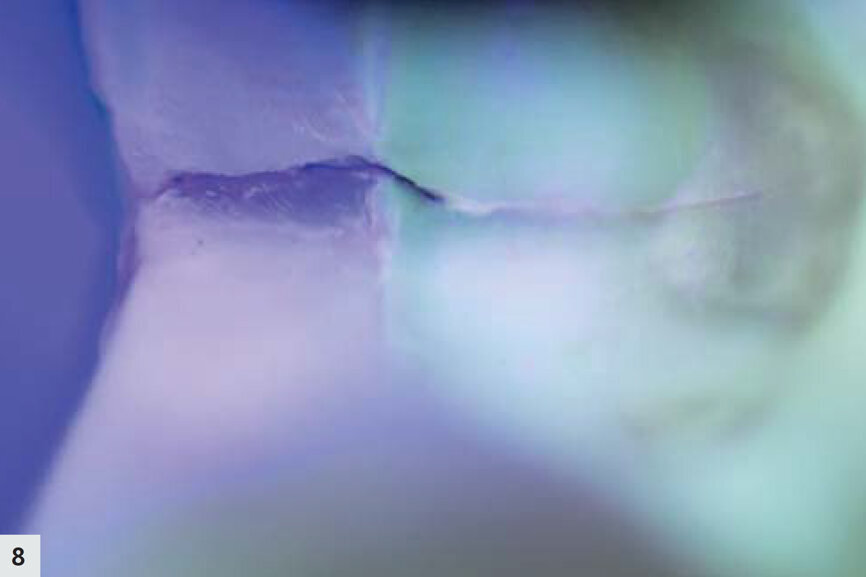

Fig. 8 : La fluorescence est sensible aux modifications structurales. La couleur violet foncée indique la partie la plus profonde de la fissure. La dentine peut être clairement délimitée grâce à la fluorescence légèrement verte.

Une autre dent présentait une profonde fissure au niveau de la limite proximale (Fig. 6). Après le nettoyage (Fig. 7), la structure était mieux visible grâce à la lampe D-Light Pro en mode détection. La structure des tissus dentaires est devenue plus apparente, la dentine émettant davantage de fluorescence dans une couleur verte bien distincte. À ce moment, on pouvait clairement observer la propagation de la fissure dans les couches plus profondes de l’émail, ainsi que dans la dentine (Fig. 8). La fissure a été mieux nettoyée puis préparée à l’aide du dispositif AquaCare Twin (Velopex) chargé avec une fine poudre de coupe d’oxyde d’aluminium, sous pression d’air et refroidissement par eau (Fig. 9). En mode détection, il est possible de confirmer en un coup d’oeil que les limites marginales de la préparation sont toutes positionnées dans l’émail sain (Fig. 10). La fissure extrêmement fine que l’on peut observer est superficielle et limitée à l’émail.